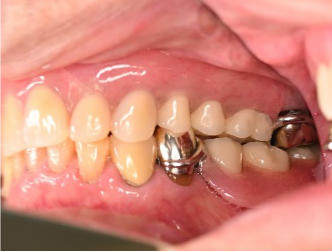

男性 Yさん 60代 (インプラント)

主訴

右下の奥歯の歯肉が痛い。時々血が出たり、腫れたりする。

治療内容

右下のブリッジの支台になっている前方の歯が、歯根破折を起こしていましたので抜歯しました。インプラントを右下第一、第二大臼歯部に2本埋入しました。

所感

実はこの患者さんは、2014年に右下の第二大臼歯(一番奥の歯から2番目の歯)を歯根破折により抜歯し、その際の治療法としてブリッジを選択されました。そして今回、ブリッジを支えていた歯(第一大臼歯)がついに歯根破折を起こしてしまいました。

ブリッジは、3本分の歯を2本の歯で支えるため、支える歯の負担が大きくなり、歯根破折を起こす危険性が高くなります。

今回の抜歯後は、歯が2本ない状態になるので、そこを補う方法についてご説明しました。選択肢は再度ブリッジを入れるか、インプラントになります。ブリッジにして支える歯がまた折れてしまうと歯が3本ない状態になる可能性があるため、インプラントを選択されました。もし11年前にブリッジではなくインプラントを選んでおられたら、今回の歯根破折や抜歯は起きなかったかもしれません。ブリッジは、噛む力の強い方、歯ぎしりをする方、硬い食べ物が好きな方は、支えの歯の負担がより大きくなるのでおすすめできません。

インプラントは、それ自身が単独で植立しているので、他の歯に負担がかかりません。インプラントは、欠損を補う最良の方法と考えます。

インプラント2本:¥726,000(税込)

Before

抜いた歯 真二つにわれています

After